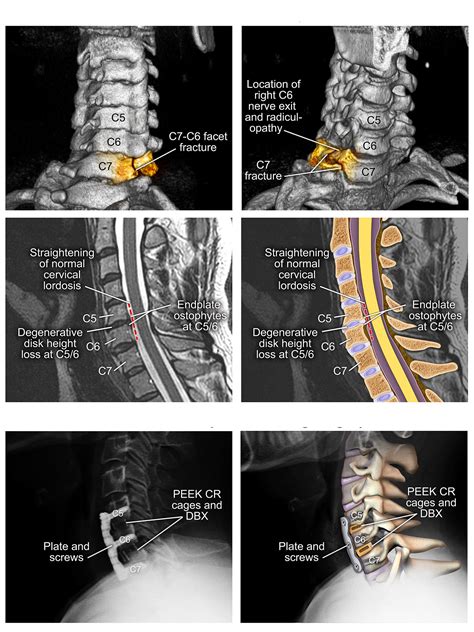

• Anterior Cervical Discectomy and Fusion (ACDF): This procedure involves removing a damaged disc from the front of the spine and fusing the adjacent vertebrae to stabilize the spine.

• Stabilization: In some cases, the surgeon may need to stabilize the spine by fusing the affected vertebrae together using bone grafts, metal plates, or screws.